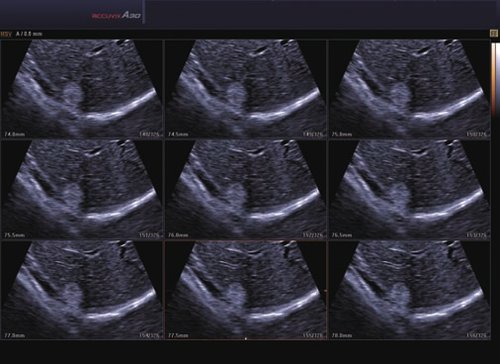

• 2D-Modus

• Die HD Volumen Bildgebung reduziert unerwünschte Streumuster und sorgt für eine präzisere Darstellung der Bilder.

• Mit DMR+™ kann das A30 höhere Kontraste und schärfere Kanten darstellen. Durch die Mehrfachfilterung werden Streumuster reduziert.